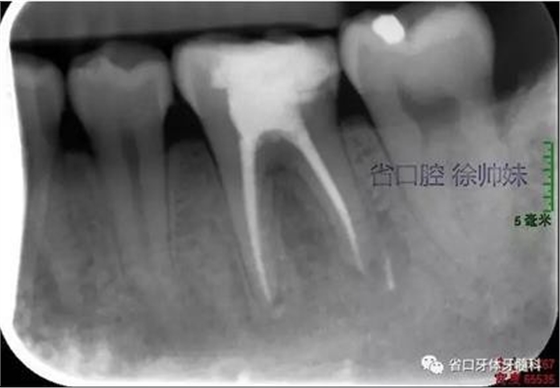

圖1 術前4月的根尖片

現(xiàn)病史:6個月前左下后牙區(qū)牙齦腫脹,反復溢膿,無明顯其他不適。4月前于我院牙體牙髓科(圖1)就診,診斷為“36牙周牙髓聯(lián)合病變”,建議試行36根管治療+牙周治療保留患牙,患者當時未行治療。現(xiàn)再次來我院牙體牙髓科要求進一步診治。

根尖片(圖2)示36大面積充填物近髓,根尖周及根分叉大面積低密度影。

圖2 術前根尖片